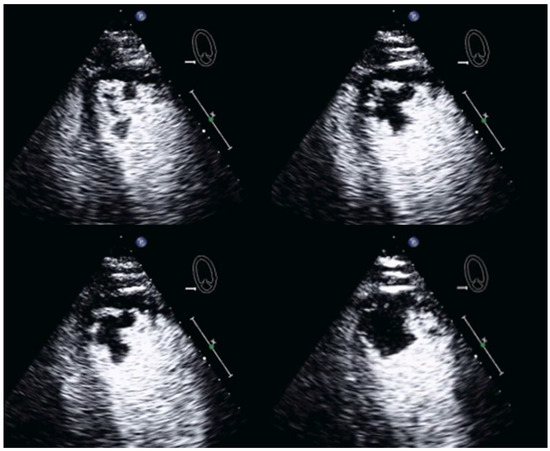

| Imaging method | Low-MI-contrast-specific imaging and intermediate-MI-contrast-specific imaging |

| Imaging planes | standard apical views additional zoomed views sweeps through the region of the suspected thrombus |

| Sector depth/width | Entire LV + 1/3 LA to assess global/regional LV function, zoomed views of the region with the suspected thrombus |

| Focus | At the depth of the suspected thrombus |

| Gain | Adjust to avoid obscuring the thrombus by intensive opacification of the cavity |

| Contrast application | bolus injections |

| Typical findings | 1. echofree mass 2. present in two different imaging planes 3. lump or laminar shape different from trabeculations’ documented size (two orthogonal diameters in at least one of the views), location, type (laminar vs. lump, single vs. multiple), surface (smooth vs. irregular) and mobility |

| DD tumor vs. thrombus | Opacified (vascularized) masses are suggestive of tumors; the vascularization can be demonstrated with myocardial perfusion imaging. CAVEAT: There are malignant tumors which appear avascular on CEUS. Tumors often are attached to normal myocardium. |

| Alternative imaging | Thrombi: Cardiac MRI when contrast echo is not possible or non-diagnostic, cardiac CT when cardiac MRI is not available Tumors: MRI provides tissue characterization and should be performed unless there is typical myxoma (attached to the interatrial septum) |